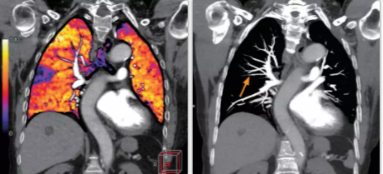

相比傳統(tǒng)成像方式,肺部柔性減影技術(shù)通過(guò)人工智能,對(duì)平掃數(shù)據(jù)和CT肺動(dòng)脈血管掃描數(shù)據(jù)進(jìn)行智能比對(duì),解碼并識(shí)別各個(gè)器官(肺、氣管、肺動(dòng)脈、肺靜脈、主動(dòng)脈等)的空間位置,并在三維空間中進(jìn)行體素級(jí)的柔性配準(zhǔn),從而極大提升了不同序列數(shù)據(jù)的空間位置的一致性。通過(guò)肺部柔性減影技術(shù)可得到肺強(qiáng)化碘圖,可以顯示出傳統(tǒng)CTPA圖像看不到的小栓塞病變,提高了栓塞檢出率,其結(jié)果甚至可與SPECT吻合。

肺智能柔性減影成像功能發(fā)現(xiàn)亞段肺栓塞